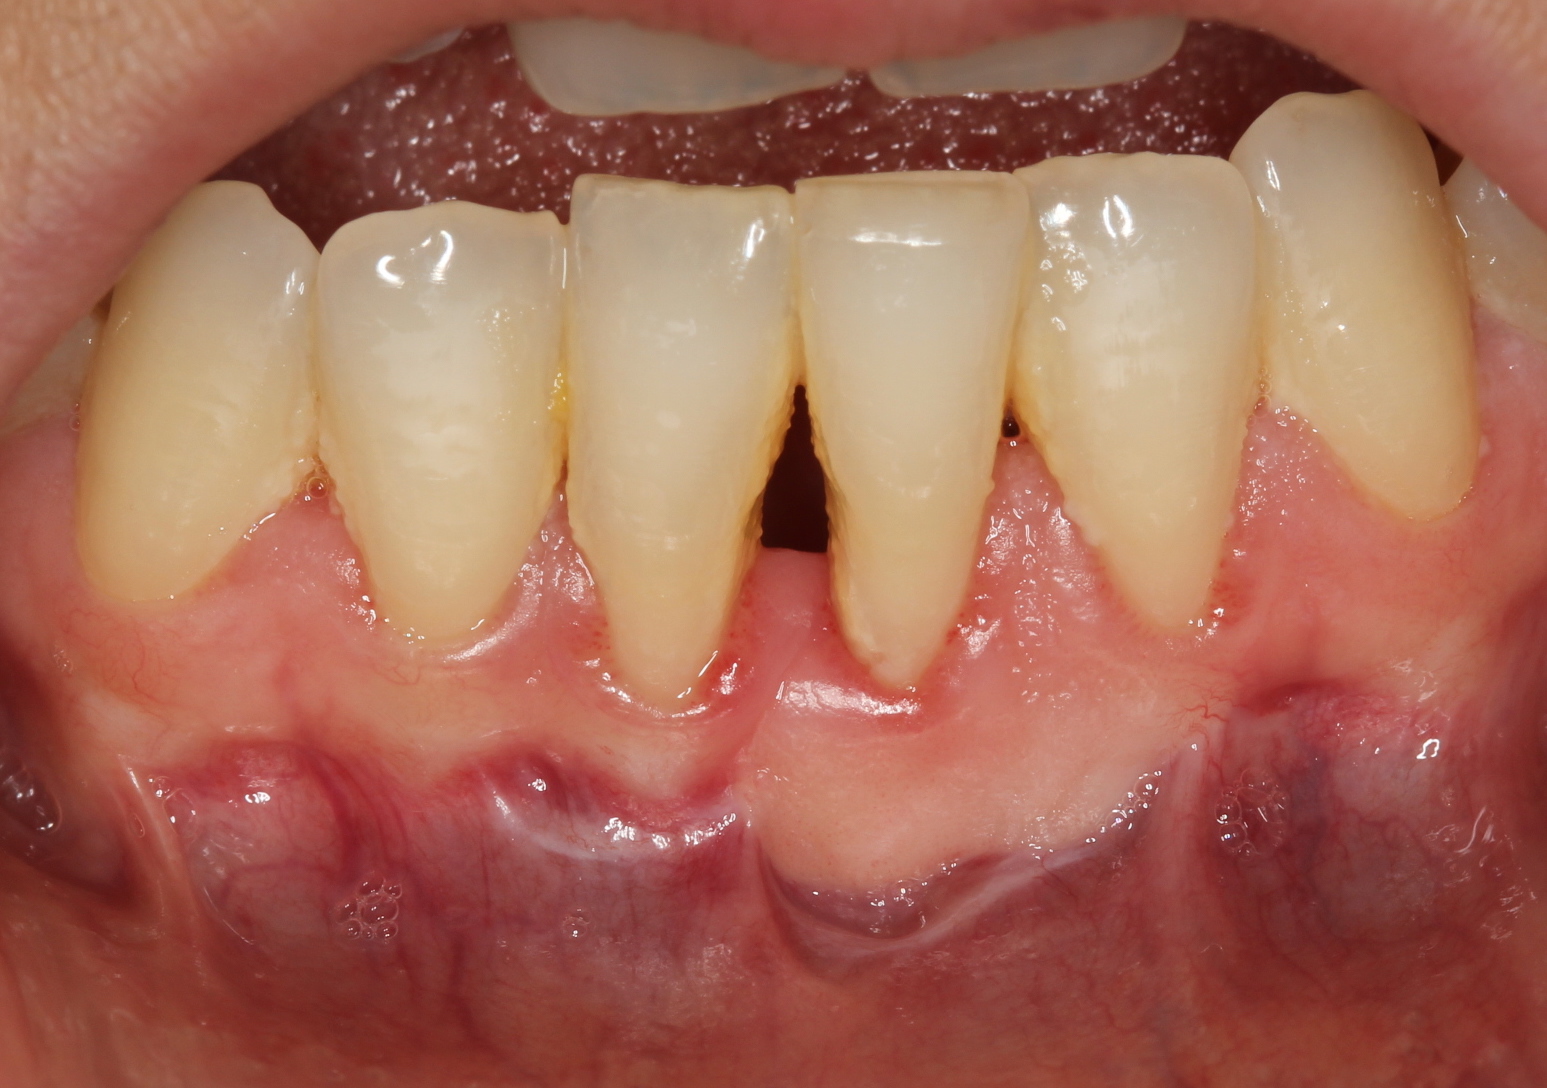

Methods: Four systemically healthy and non-smoker patients were referred to Abant İzzet Baysal University, Faculty of Dentistry, Department of Periodontology. Graft was harvested from palate and periodontal dressing wasn’t used. After surgery patient received LLLT using a 820nm diode laser, with output power of 1 W. immediately after surgery, on the first day, on the 7th day and lastly on the 14th day. Probing depth and FGG dimensions (horizonto-superior (HS), horizonto-inferior (HI), and vertical (V)) were assessed by using digital caliper at the same reference point and recorded before surgery, 1 and 3 months postoperatively.

Results: Although in this study we didn’t use periodontal dressing, healing was uneventful and patients' discomfort was minimum. Free gingival graft with assist of low level laser therapy show promising result for all following intervals. Graft dimensions were 10.00mm, 11.75mm and 6.25mm before the surgery; 8.5mm, 12.37mm and 5.87mm within the first month; 8.33mm, 9.66mm and 5.33mm within first three months for HS, HI and V; respectively. Normality of distribution was tested with the Shapiro–Wilk procedure. Kruskal-Wallis was used for the intergroup comparisons. There were no significant differences between the time interval.

Conclusions: The results showed that LLLT was an effective adjunctive treatment in promoting revascularization during early healing of FGG. In addition these results may support the idea of low-level laser therapy as a supportive therapy in patients receiving free gingival graft.